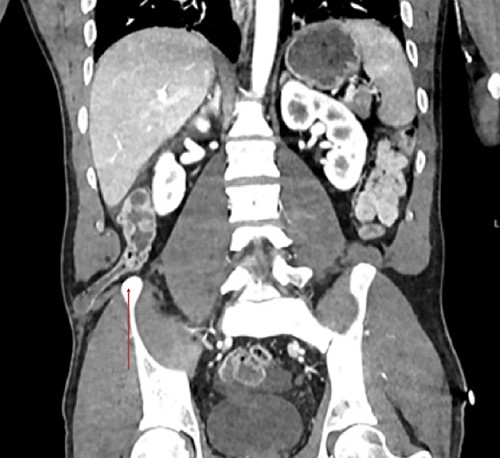

Traumatic lumbar hernias are quite uncommon, as such most surgeons are unfamiliar with them. This was a 41-year-old male Caucasian who was involved in a head on vehicular collision of estimated velocity of 140 mph. Computed tomography (CT) trauma scan confirmed a lumbar hernia through the inferior triangle of petit containing the ascending colon (Figs 1–3). Multiple bony fractures were also noted on the imaging. In discussion regarding the management of the hernia, it was felt that urgent repair was needed to avoid bowel ischaemia or perforation, rather than delayed repair. To repair the defect a laparoscopic approach was initially trialled, (transabdominal repair). Peritoneum was incised around the hernial defect to access the extra-peritoneal space. The hernial sac was dissected; bowels showed no macroscopic signs of ischaemia or injury in the sac. However there was major avulsion of muscles from the iliac crest (>15-cm defect; Fig 1), which was closed posteriorly. Anteriorly it was difficult to close the defect as it was difficult to suture the muscles on to the periosteum of the iliac crest. A decision was made to convert to open surgery as to better access the muscles for suturing. Ventralight mesh was placed extra-peritoneally for further enforcement. The right inferior epigastric vessels were also notably torn, which were tied. Torn right rectus muscles were also approximated and sutured. Peritoneum was closed. This repair was performed extra-peritoneally.

Coronal view showcases the inferior lumbar hernia above the iliac crest (red arrow).